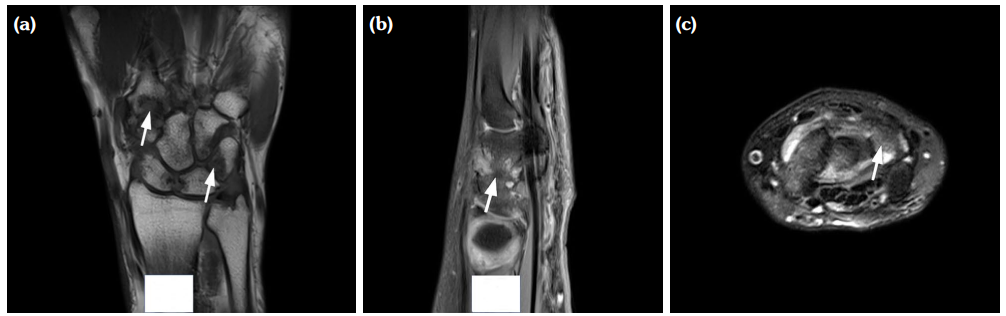

The degree of BE and synovial hyperplasia in SNRA or SPRA is more serious, and the blood flow signal is more abundant. However, the degree of synovial hyperplasia in osteoarthritis was mild, and no obvious blood flow signal was detected (Figures 1, 2, 3 and 4). Magnetic resonance imaging (MRI) studies of SPRA also showed serious BE (Figure 5).

One of the limitations to this study is the lack of other imaging and pathological comparisons. Magnetic resonance imaging is an effective tool to examine early RA and to evaluate therapeutic effect; it is considered gold standard for RA research. However, in practice, it is time-consuming to perform MRI examinations on all the affected joints of the patient's hands. Moreover, MRI can be costly for many patients. On the other hand, although needle biopsy of joint synovium is helpful for accurate diagnosis of disease, it is an invasive operation with high technical requirements for the operator and may, thus, not be the best choice for patients.